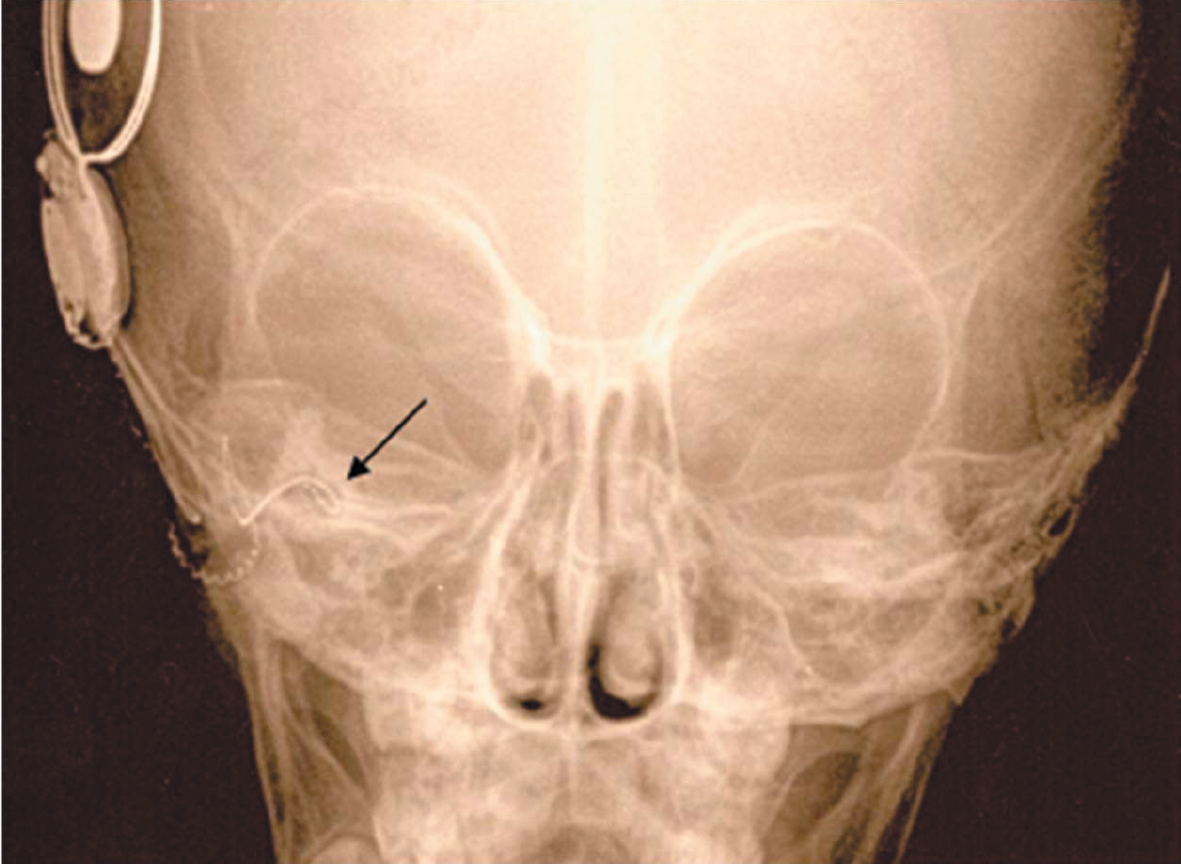

According to various authors, 20% of children with sensorineural hearing loss or deafness, anomalies in the structure of the temporal bones are determined according to the results of computed tomography. Cochlear implantation in the presence of cochleovestibular malformations is associated with a number of difficulties. These include the peculiarities of cochleostomy and placing of the electrode inside the cochlea, the risk of damage to the facial nerve due to its abnormal location, intraoperative liquorrhea, which can lead to the development of bacterial meningitis in the postoperative period, as well as the risk of penetration of the electrode into the internal auditory canal. In this research, we present our method of performing cochlear implantation in case of a malformation in the development of the inner ear (common cavity). The method expands the possibilities of cochlear implantation for e auditory perception in patients with this pathology.